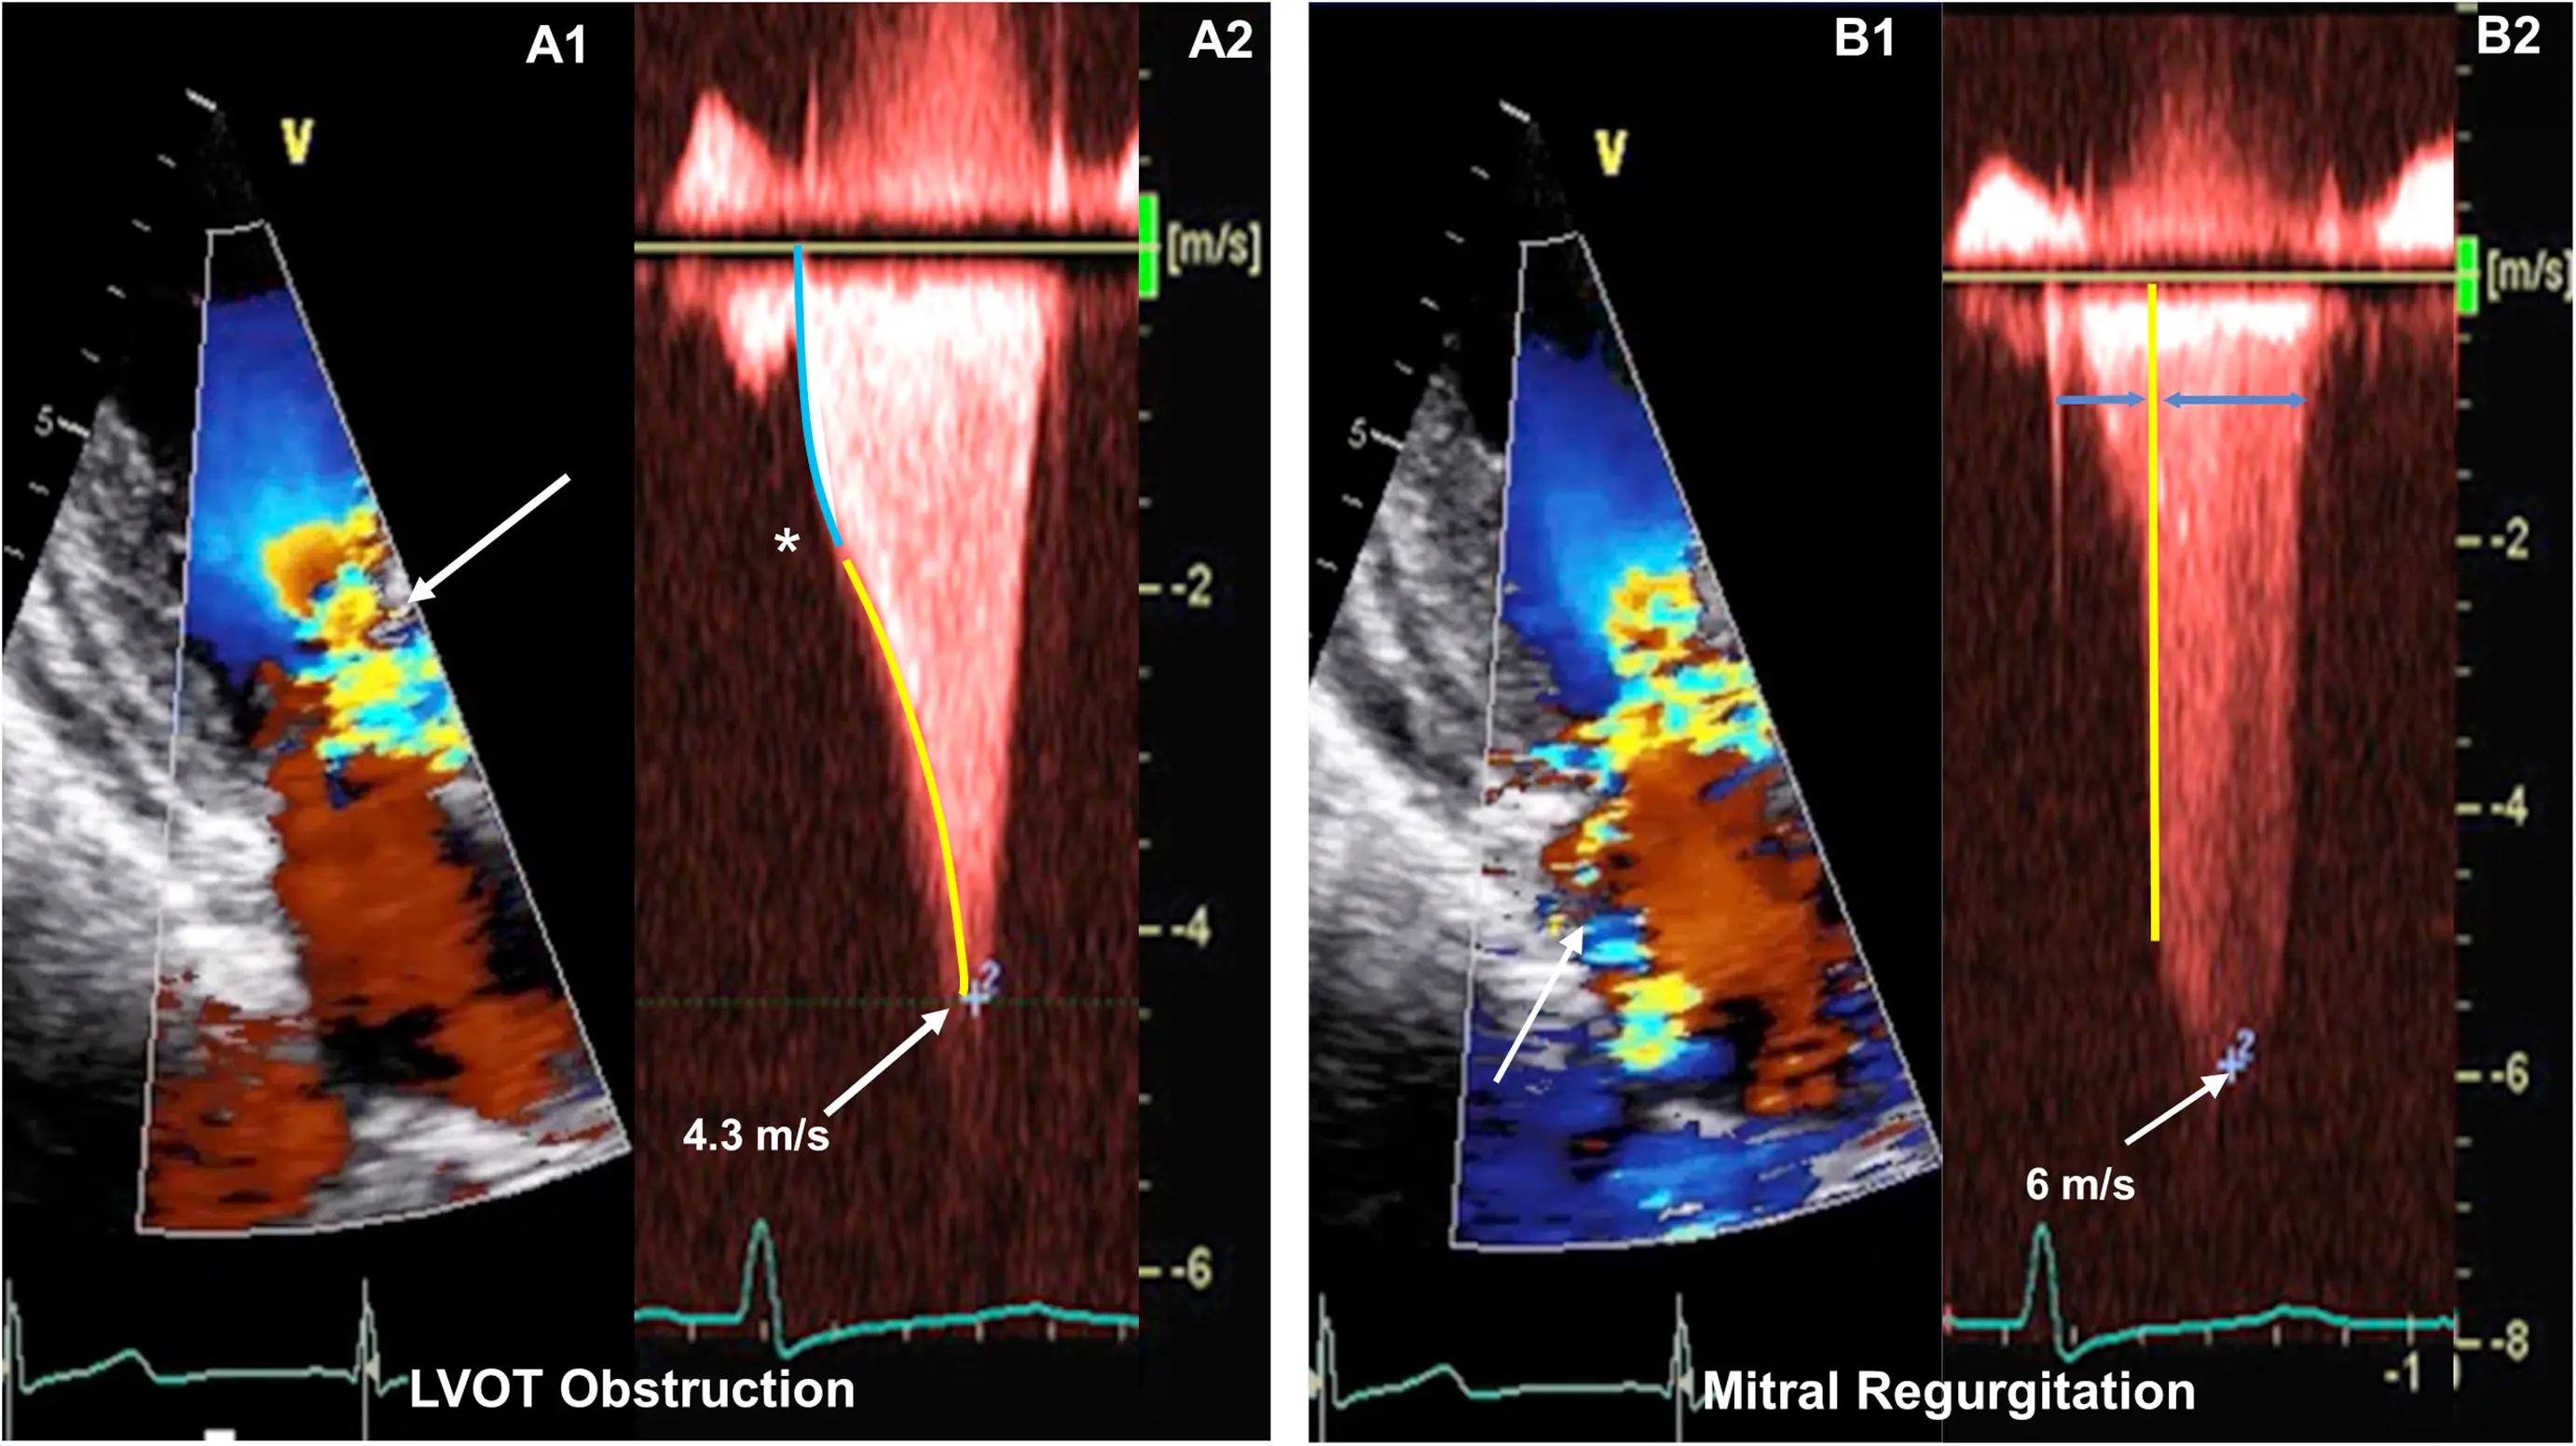

⚠️ LVOTO in HCM is dynamic and sensitive to ventricular preload, afterload, and contractility. 2 Thus, gradients vary with heart rate, blood pressure, volume status, activity, medications, food, and alcohol intake.

Classically described as having a “dagger”-shaped appearance, but honestly resembles more of a nonworking upper edge of a Bowie knife. 2 Dr. Saghir also used the term “dragon’s tooth,” which I like.

Gradients > 60 mmHg may take on a “lobster claw” pattern 2

Pulsed Wave Doppler of the thoracic aorta

- Double-peaked, “spike-and-dome” pattern

Acceleration of flow → Absence of flow → Flow again, aka “lobster claw”